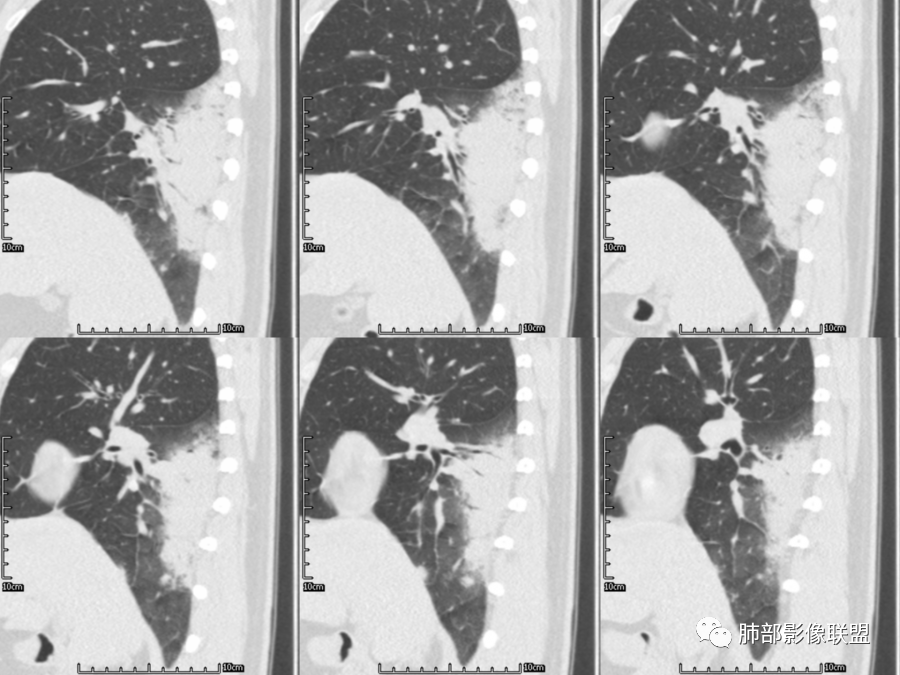

大叶性肺炎是外周向中心的,与胸膜垂直的,沿着气道方向,隐球菌是平行胸膜的,我感觉是肺小叶内的肺泡起源

南边

隐球菌沿胸膜下分布,不受段的局限,沿肺实质朝周围蔓延

初学者

细菌性肺炎是沿着支气管往周围肺泡散开,内朝外,沿着叶段分布,受到支气管管辖,呈扇形,与支气管长轴平行,与胸膜垂直,隐球菌就是外朝内,外就是肺小叶内的肺泡,外周的。

肺小叶。他就是一个个肺小叶的融合,胸膜平行,和病毒一样。只是病毒在间质,是肺小叶分布的毛玻璃。隐球菌是肺实质,肺泡,肺小叶的实变。

这个病变换个角度看

首先小叶性肺炎是什么概念-细支气管末端、腺泡结节的一些病变引起的。一定会合并树芽征等细支气管的改变。

这个病例呢?没有。如若考虑细菌性的,那还是应该是大叶性的,靠近大支气管蔓延的。小叶性融合的,也还是有细支气管的一些特点出来。

病毒呢,有个特征意义的-细网格征。磨玻璃区域的病变内是沿间质蔓延为主的特点。

这个病例周围磨玻璃病变仅有几个小叶间质增厚,没有细网格征,还是肺实质病变为主,小叶内间质增厚不明显,从分布特点就不符合。

这个病变也不是一个起源中心,胸膜下,多发结节状、实变影。而大叶性肺炎多数由内-外大片状。所以是肺实质多发融合病变。单纯从影像上,还是比较符合隐球菌特点,胸膜下,多发、多中心,相互融合(兄弟齐心)。

我感觉大叶性肺炎是偏高位的中心一点的内向外。病毒是外向内的间质(肺小叶层面),隐球菌这种是外向内实质(位置偏外偏下的肺泡,多灶的融合)

你看实性部分,有很多小结节的实性部分,分布很散,不是一个区域,不是按一个段过来的,是多个段,但是内基底段似乎又不受累。所以大叶性肺炎,一般细菌性的这个影像特点还是不太支持。

隐球菌,胸膜下病灶,多个起源中心,最终还是融合在一起,侧向融合为主的。

细菌性,小叶性肺炎,小气道为主,小气道壁受累、支气管腔内狭窄之类的,周围间质变化等。是一个个小支气管受累及。大叶性不是这样的,都是大片状、范围广,很快从外向内沿气道蔓延,受管腔约束,总体是按叶段蔓延的,很少有树芽征。

隐球菌,侧向融合、外围胸膜下为主,也有累及叶段的、比较少。

隐球菌之顺口溜(影像征像版)在那遥远的边远山区——胸膜下生活着一群蘑菇兄弟——性质相同多结节表面虽脏,内心实诚——有晕,一般无空洞扮扮鬼脸,偶尔调皮——鬼脸征撞墙就跑,颇有灵性——一般不引起胸膜增厚积液气管通畅或进门才堵,只为空气——不会堵门口周围蔓延,不乱播散,死心踏地——不走淋巴,气管,血道播散。污头垢面,家里干净,只因免疫不低,神采奕奕——空洞干净,注意:以上不适用于免疫力低下病人。